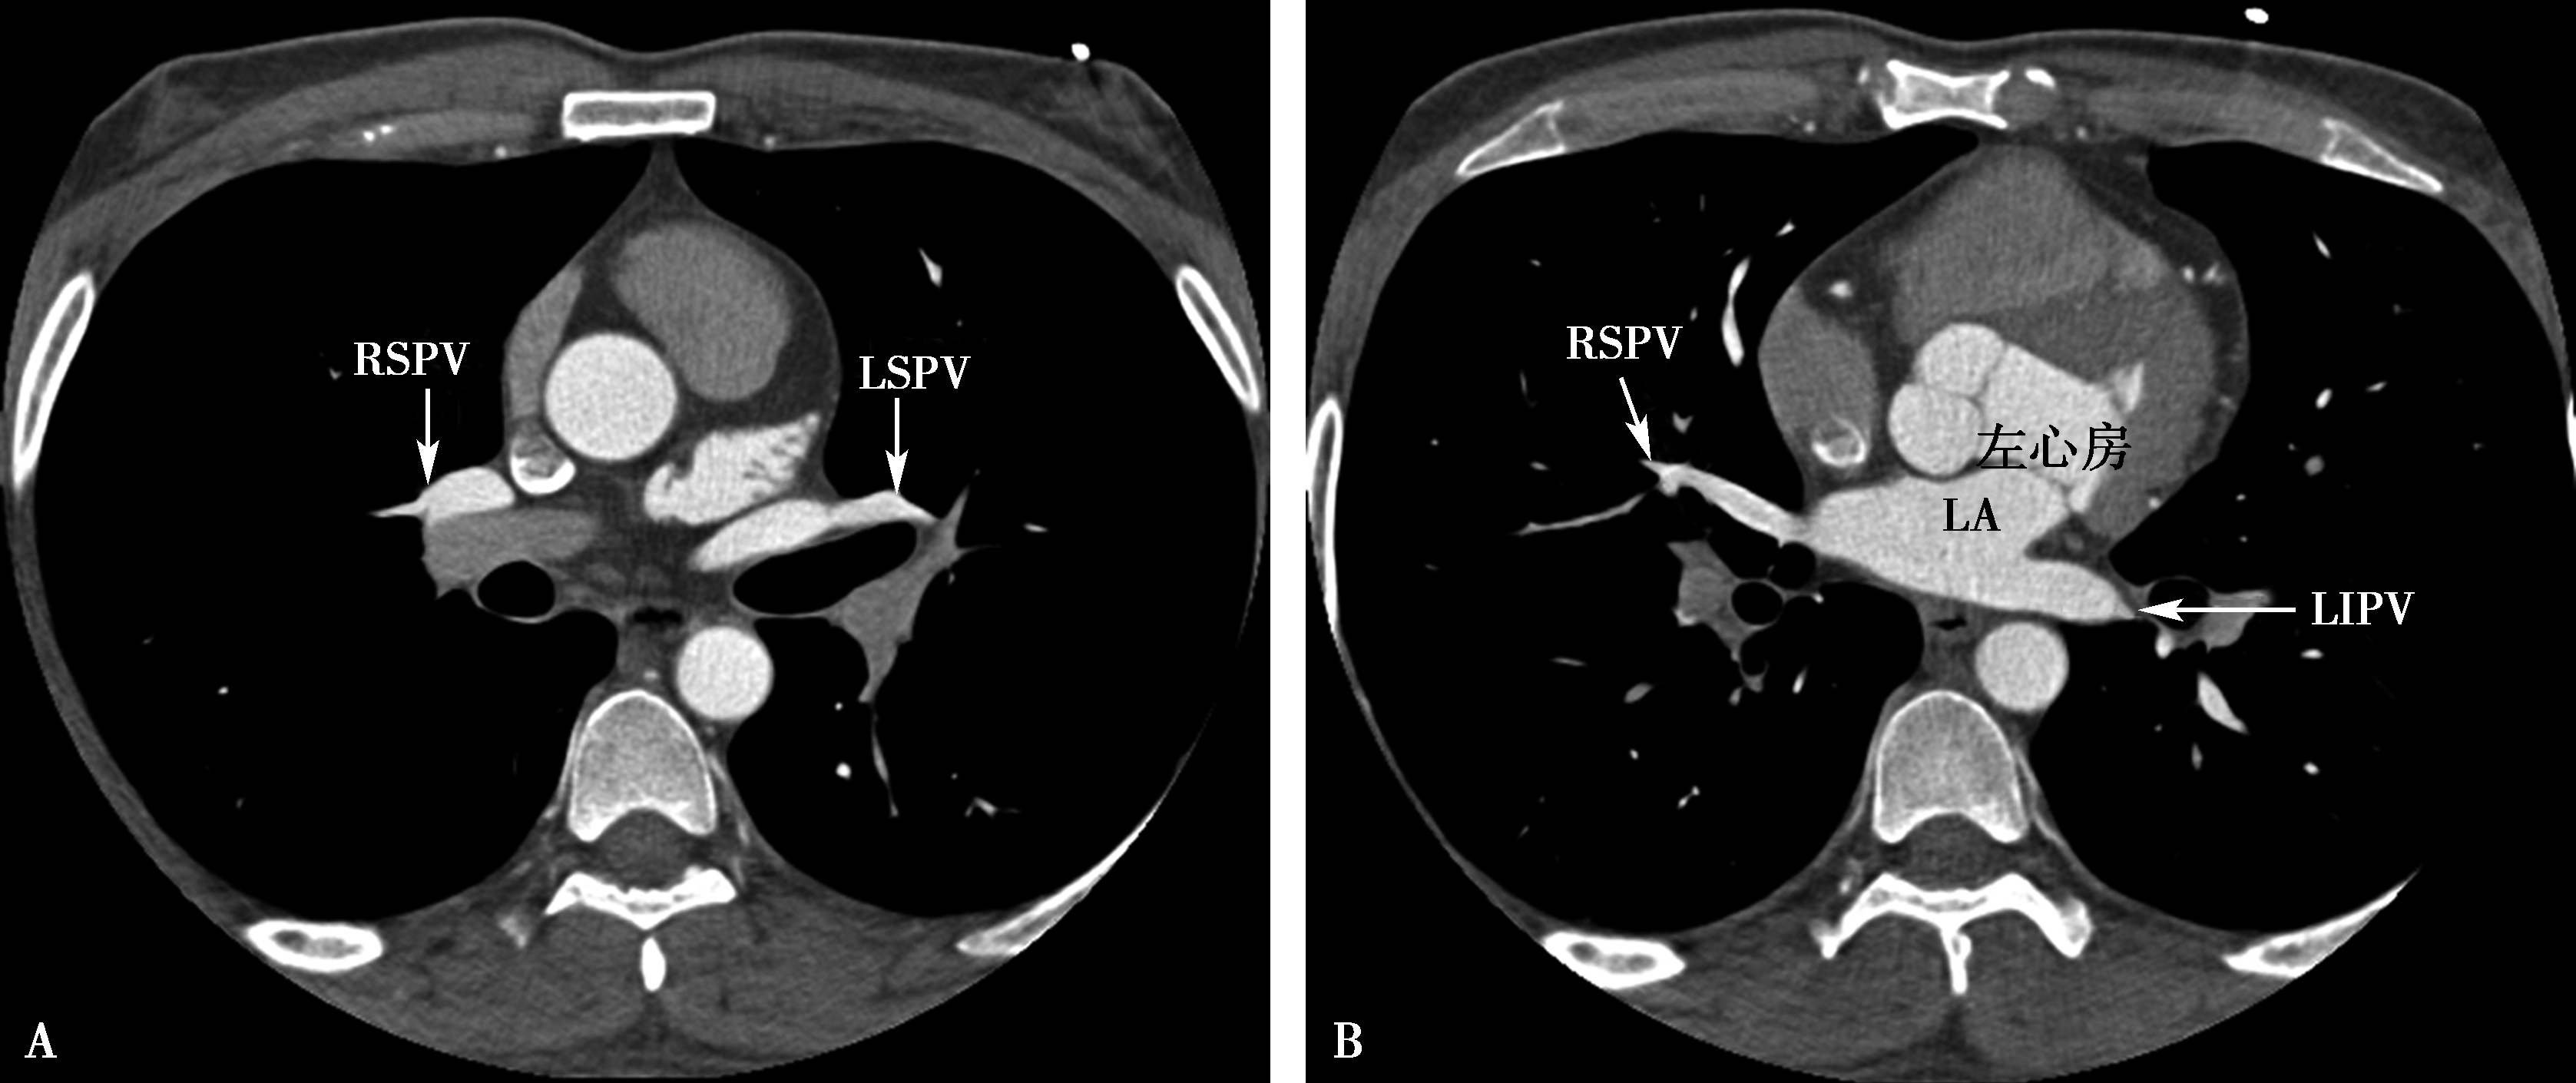

图8-2-10 肺静脉横断像

A.升主动脉层面;B.主动脉根部层面;C.左心房-二尖瓣层面;D.左心房-二尖瓣层面。RSPV:右上肺静脉;RIPV:右下肺静脉;LSPV:左上肺静脉;LIPV:左下肺静脉;LA:左心房